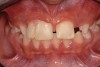

Fig 1 and Fig 2. Pretreatment photographs. Patient at 9 years of age on presentation.

A 9-year-old girl, referred to a prosthodontic office by her pediatric dentist, presented with her mother’s chief complaint: “The kids are teasing her about her big front tooth.” Findings from radiographic and clinical examinations revealed fused maxillary central-peg lateral incisors, teeth Nos. 7 and 8, and a congenitally missing lateral incisor, tooth No. 10 (Figure 1 through Figure 3). An implant was selected as the ideal treatment to replace tooth No. 10 when somatic growth was complete. A diagnostic wax-up was fabricated to determine if the fused tooth could be made to resemble two teeth, using pink composite to give the illusion of an interproximal papilla. The patient was referred for an orthodontic consultation to plan for closure of the diastema between teeth Nos. 8 and 9 and achievement of proper alignment for implant No. 10. The patient was also referred to a periodontist for pretreatment assessment of the tooth No. 10 site. An endodontist was consulted should exposure of the large pulp occur during tooth preparation.